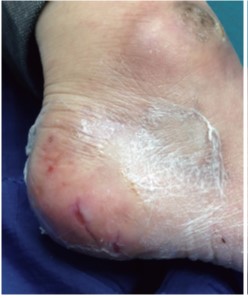

|パクリタキセル+セツキシマブ治療中の踵の亀裂に対するポリウレタンフィルム処置

外用薬なしでポリウレタンフィルムを貼るだけで痛みが軽減し、治癒も促進される。フィルム下に滲出液が溜まるようであれば毎日フィルムを除去し、石鹸で洗浄後貼り直す。滲出液が溜まらなければ1〜2日交換しなくてもよい。絆創膏などで皮膚が白くふやけると乾燥後に亀裂は悪化する。